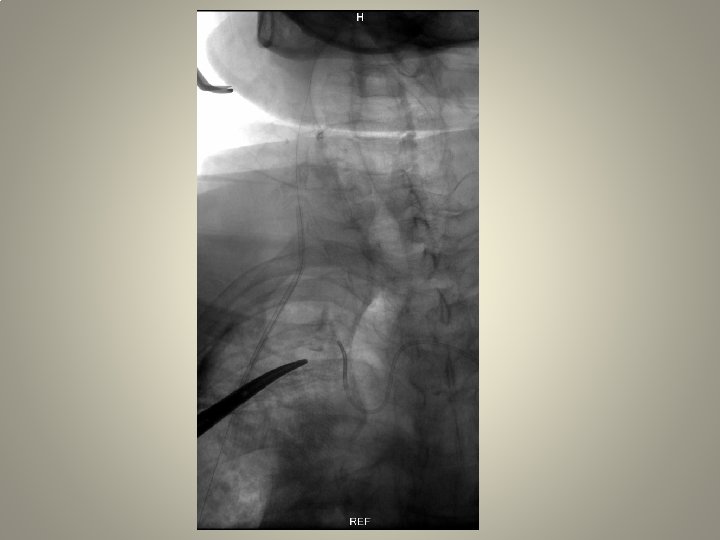

Neden stent? TANDEM lezyon

Vasküler erişim • Kateterizasyon: uzun re-inforced sheats (terumo, arrow, cook) uzun diagnostik kateter 120/125 cm Hidrofilik (Terumo 0. 035 -38 stiff or roadrunner-Cook) teller Hidrofilik olmayan (amplatz) teller

Uzun kılıf • Standard kılavuz kateterlere oranla artmış stabilite • Geniş lümen • Bükülmeye direnç • Hidorfilik kayganlık, ilerletilebilme

Uzun kılıf • Terumo Destination 6 F, 90 cm, iç lümen • Cook Shuttle, 5 F 90 -110 cm, 0. 074 inch 6 F 80 -110 cm, 0. 087 inch • Arrow…….